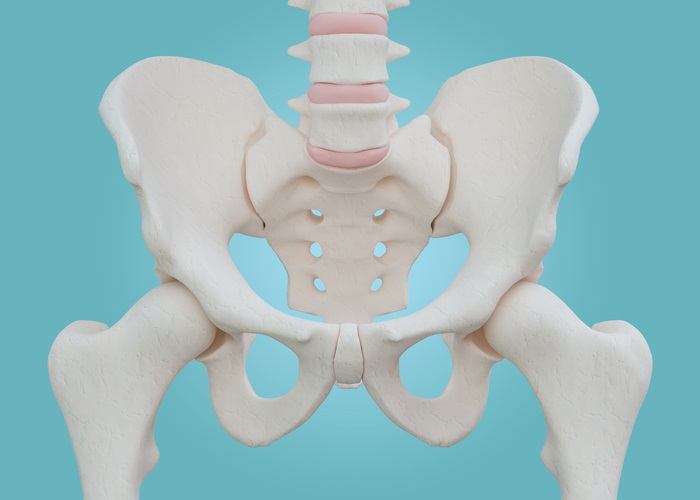

고관절 수술은 많은 환자들에게 삶의 질을 향상시킬 수 있는 중요한 과정입니다. 그러나 이 수술 후의 회복 기간은 개인의 건강 상태, 수술 방법, 동반 질환, 그리고 개인의 생활 습관 등 다양한 요인에 따라 다르게 나타날 수 있습니다. 이 글에서는 고관절 수술 후 회복 기간을 여러 측면에서 살펴보며, 각 단계에서 필요한 주의 사항과 방법론 등을 상세히 설명할 것입니다. 수술 후의 회복 과정을 이해하는 것은 환자에게 큰 도움이 되며, 보다 효과적인 회복을 도모할 수 있습니다. 또한, 회복 과정에서 겪는 다양한 증상과 그 대처 방법에 대한 정보도 포함할 예정입니다. 이제 고관절 수술 후 회복기간에 대한 전체적인 그림을 그려보겠습니다.

고관절 수술은 다양한 이유로 시행될 수 있지만, 일반적으로는 고관절 관절염, 외상, 또는 선천적인 기형 등으로 인해 통증이나 기능 저하가 나타날 때 이루어집니다. 이 수술에는 인공관절 치환술, 관절경 수술 등의 방법이 있으며, 각각의 수술 방법은 회복 단계와 필요한 시간에 서로 영향을 미칩니다. 고관절 수술의 주된 목적은 통증을 감소시키고, 이동성과 일상생활의 질을 향상시키는 것입니다. 그러므로, 환자는 수술 후 생활 습관을 조절하고, 적극적인 rehabilitative 간호를 통해 빠른 회복을 도모해야 합니다.